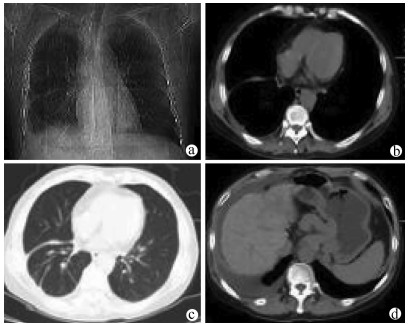

Postoperative complications of ex vivo liver resection combined with autologous liver transplantation in treatment of advanced hepatic alveolar echinococcosis at high altitude and related prevention and treatment strategies

Qingshan TIAN, Shaopei FENG, Yamin GUO, Xiumin HAN, Shunyun ZHAO, Chengjie YE, Yongde AN, Shile WU, Xiangqian WANG, Haibo ZHENG, Wenjun ZHU, Jide A, Wei GAO, Hongshuai PAN

2021, 37(9): 2153-2160. DOI: 10.3969/j.issn.1001-5256.2021.09.029

Abstract(1294) HTML (489) PDF (3321KB)(53)

Abstract:

Objective  To investigate the postoperative complications of ex vivo liver resection combined with autologous liver transplantation in the treatment of end-stage hepatic alveolar echinococcosis at high altitude and related prevention and treatment strategies.  Methods  Surgical data and follow-up data were collected from 11 patients with end-stage hepatic alveolar echinococcosis who underwent autologous liver transplantation in Qinghai People's Hospital from January 2013 to March 2019, and intraoperative and postoperative conditions were analyzed.  Results  All 11 patients underwent autologous liver transplantation successfully, without intraoperative death, among whom 2(18.18%) underwent hemi-extracorporeal hepatectomy and 9 (81.82%) underwent total extracorporeal hepatectomy. For the reconstruction of the retrohepatic inferior vena cava, 2 patients (18.18%) underwent reconstruction with the autologous great saphenous vein, 4 patients (36.36%) underwent reconstruction with artificial vessels, and the autologous retrohepatic inferior vena cava was preserved in 5 patients (45.45%). For biliary reconstruction, 8 patients (72.73%) underwent choledochoenterostomy and 3 (27.27%) underwent choledochocholedochostomy. The main postoperative complications of the 11 patients included bleeding in 2 patients (18.18%), bile leakage and abdominal infection in 4 patients (36.36%), bilioenteric anastomotic stenosis in 1 patient (9.09%), thrombus in 2 patients (18.18%), pulmonary infection and pleural effusion in 2 patients (18.18%), and echinococcosis recurrence in 1 patient (9.09%). Of all 11 patients, 2 (18.18%) died during the perioperative period, and the other 9 patients (81.82%) were improved and discharged.  Conclusion  Bleeding, biliary complications, and infection are the main causes of death in patients undergoing autologous liver transplantation at high altitude. An accurate understanding of surgical indication, careful multidisciplinary evaluation before surgery, superb operation during surgery, standardized surgical procedures, and fine perioperative management are the key to reducing perioperative mortality, avoiding and reducing postoperative complications, and achieving good long-term survival in patients undergoing autologous liver transplantation.